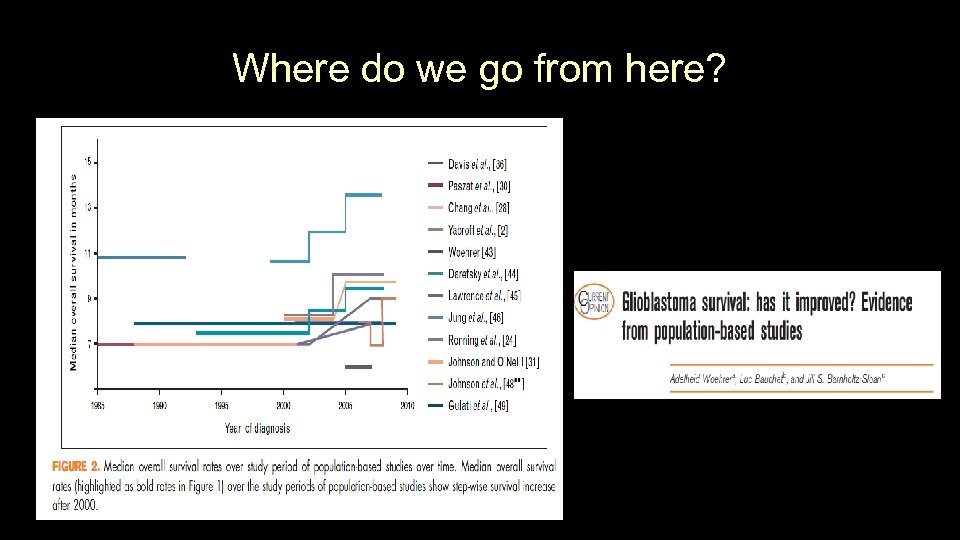

Where do we go from here?